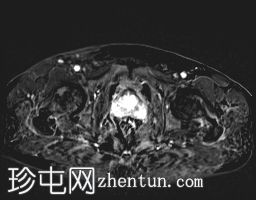

轴位

T2加权像

外周带 (PZ):

T2WI:双侧外周带弥漫性、不均匀低T2信号,范围>15 mm,尖端后内侧可见小片相对保留的病灶。左侧尖端及腺体中部可见包膜隆起。评分5/5。

DWI/ADC:高b值DWI呈弥漫性高信号,ADC呈相应低信号(扩散受限)。评分5/5。

DCE:早期强化阳性。

PI-RADS:5 - 极高风险(极有可能存在临床意义的癌症),考虑炎症性病变。

肉芽肿性前列腺炎是多参数磁共振成像 (mpMRI) 中一种重要的、与临床意义显著的前列腺癌相似的疾病,因为它可以产生明显的周围带异常,伴有扩散受限和早期强化,通常导致较高的 PI-RADS 分级。

在本病例中,mpMRI 显示双侧周围带弥漫性 T2 低信号,高 b 值 DWI/ADC 图像上呈扩散受限,早期强化阳性,并伴有包膜轮廓隆起。这种影像学表现可能类似于浸润性或广泛性周围带癌,尤其是在 PSA 升高和直肠指检异常的情况下。然而,炎症性疾病,特别是肉芽肿性前列腺炎,可能出现类似的影像学表现。经直肠前列腺活检的组织病理学检查显示,患者患有严重的慢性非干酪性肉芽肿性前列腺炎,未见肿瘤证据。